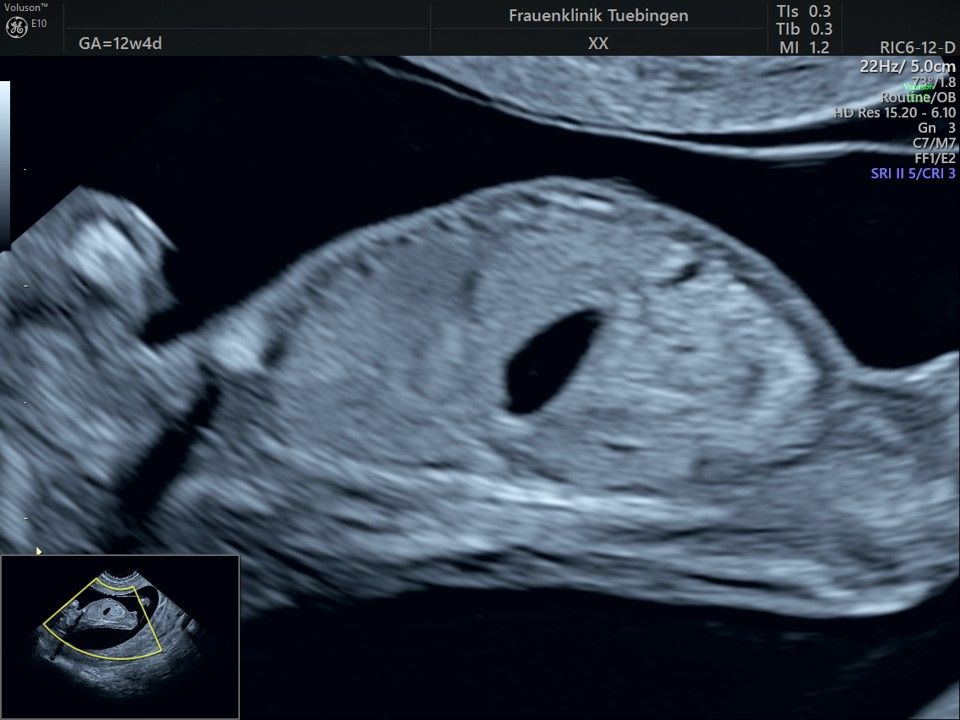

Im Rahmen des Ersttrimester-Screenings untersuchen wir die Organe des Feten mittels Ultraschall. Dabei machen wir auch gerne ein Bild für Sie.

Obwohl der Fet zu diesem Zeitpunkt erst zwischen 5 und 8cm groß ist, lassen sich bereits etwa die Hälfte aller schwerwiegenden Fehlbildungen erkennen bzw. ausschließen. Sollten wir eine Auffälligkeit sehen, werden wir mit Ihnen den Befund und das weitere Vorgehen ausführlich besprechen.

Fetale Anatomie